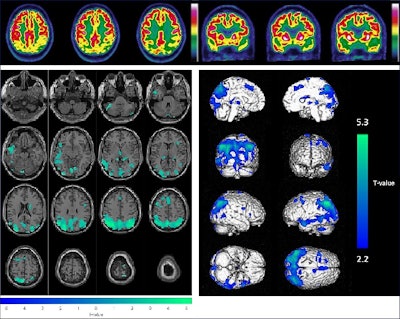

Example of the combined visual (upper panel, axial and coronal slices of brain F-18 FDG-PET images) and semiquantitative (lower panel, with hypometabolisms in green projected on axial MRI slices on the left and hypometabolisms in blue on a 3D volume rendered on the right) analysis for a 65-year-old male patient (initially diagnosed with mild cognitive impairment); these results were consistent with Alzheimer’s disease. The final diagnosis was Alzheimer’s disease and conversion to dementia after 31.5 months.Image and caption courtesy of Alzheimer's Research and Therapy.